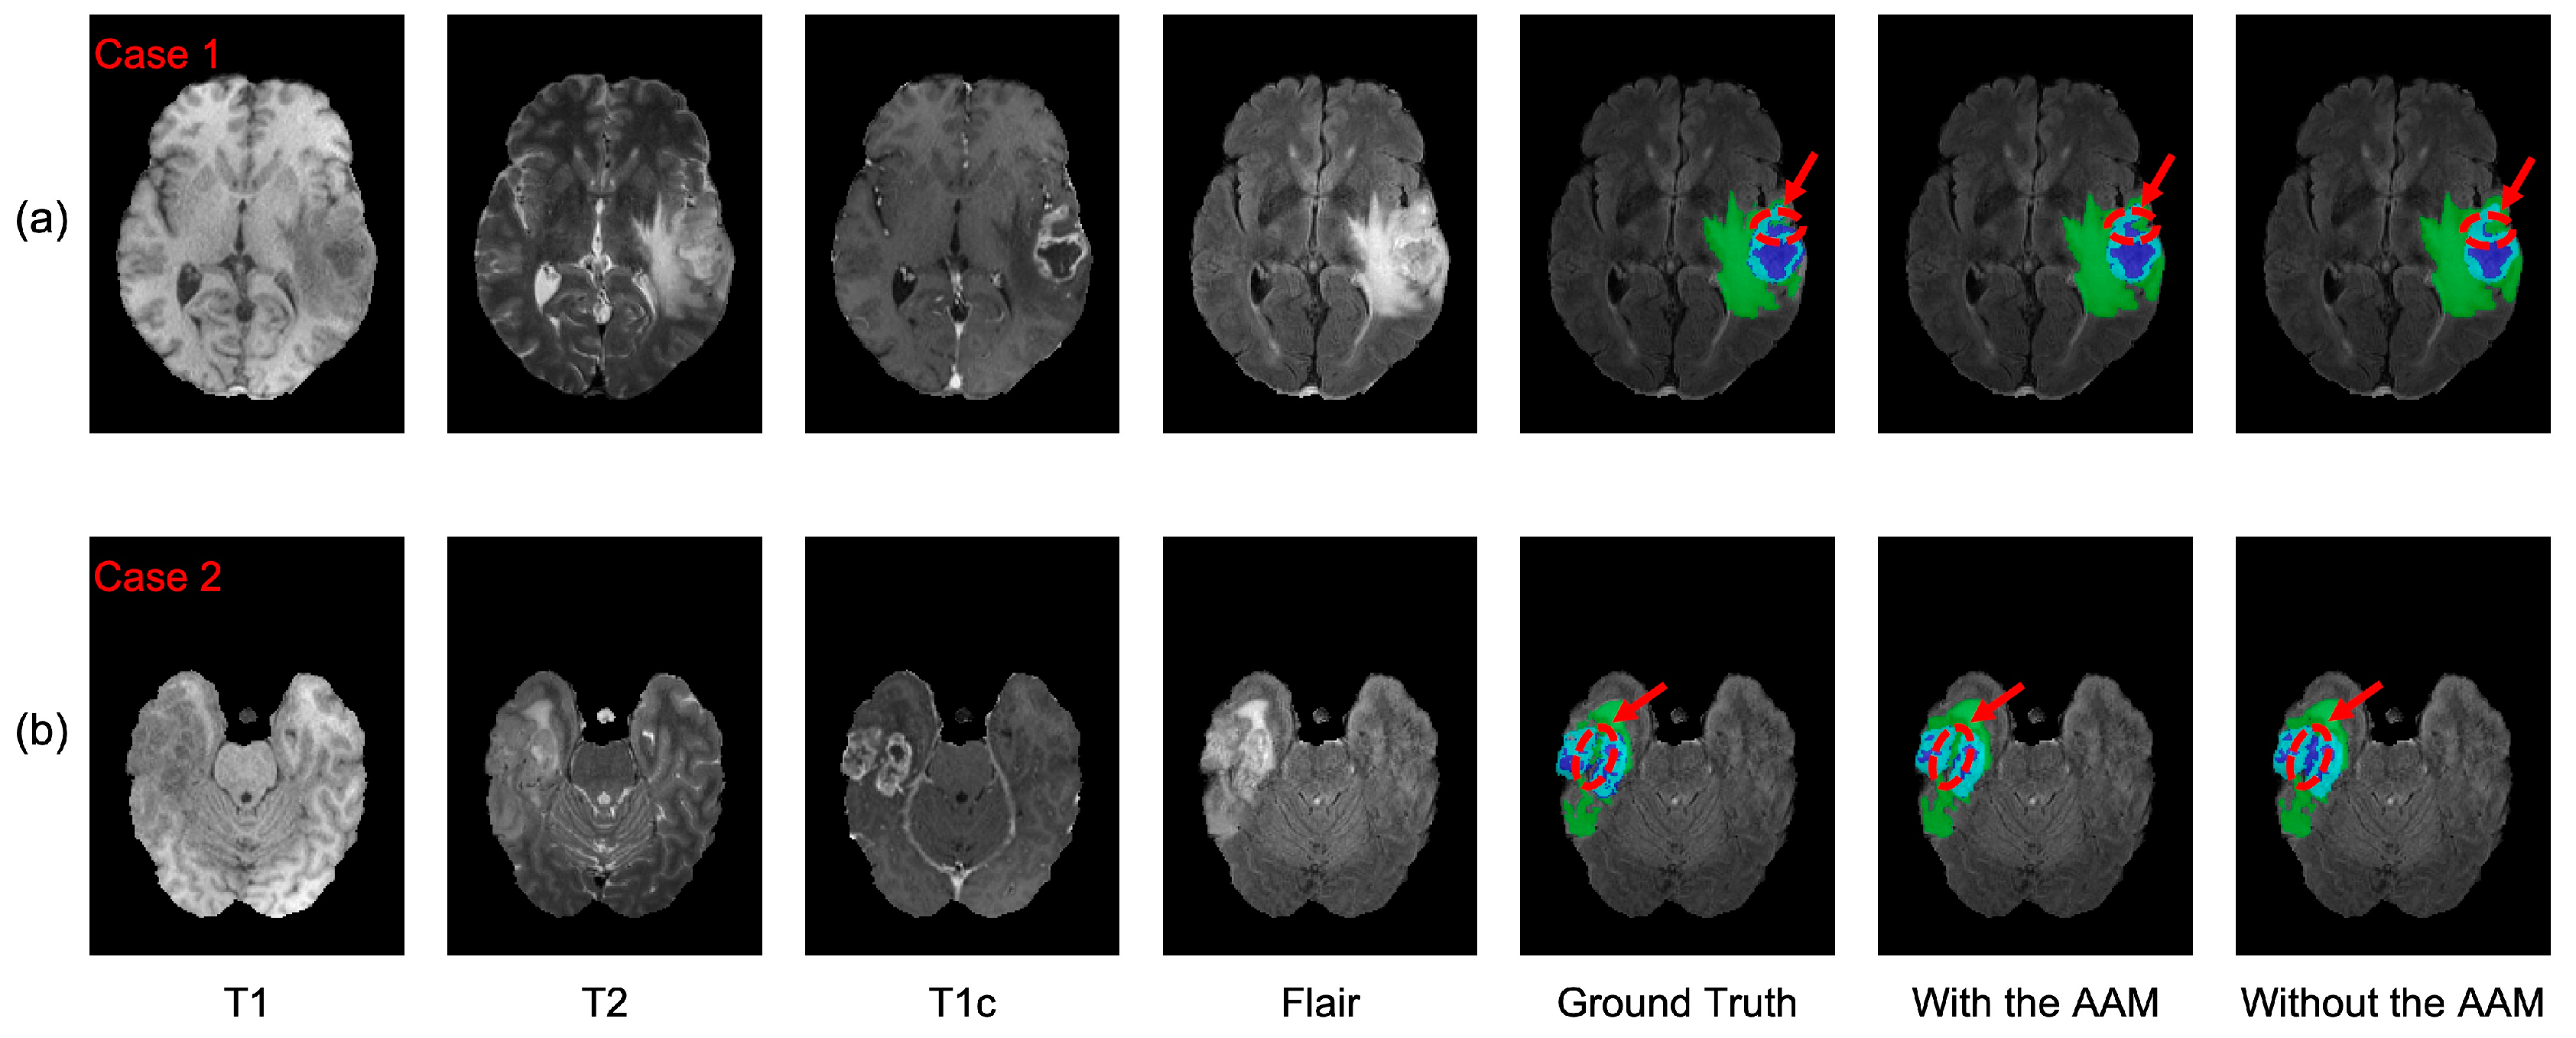

4.2.1. Analysis of the Axial Attention Mechanism

4.2.2. Analysis of the Deep Supervision Mechanism